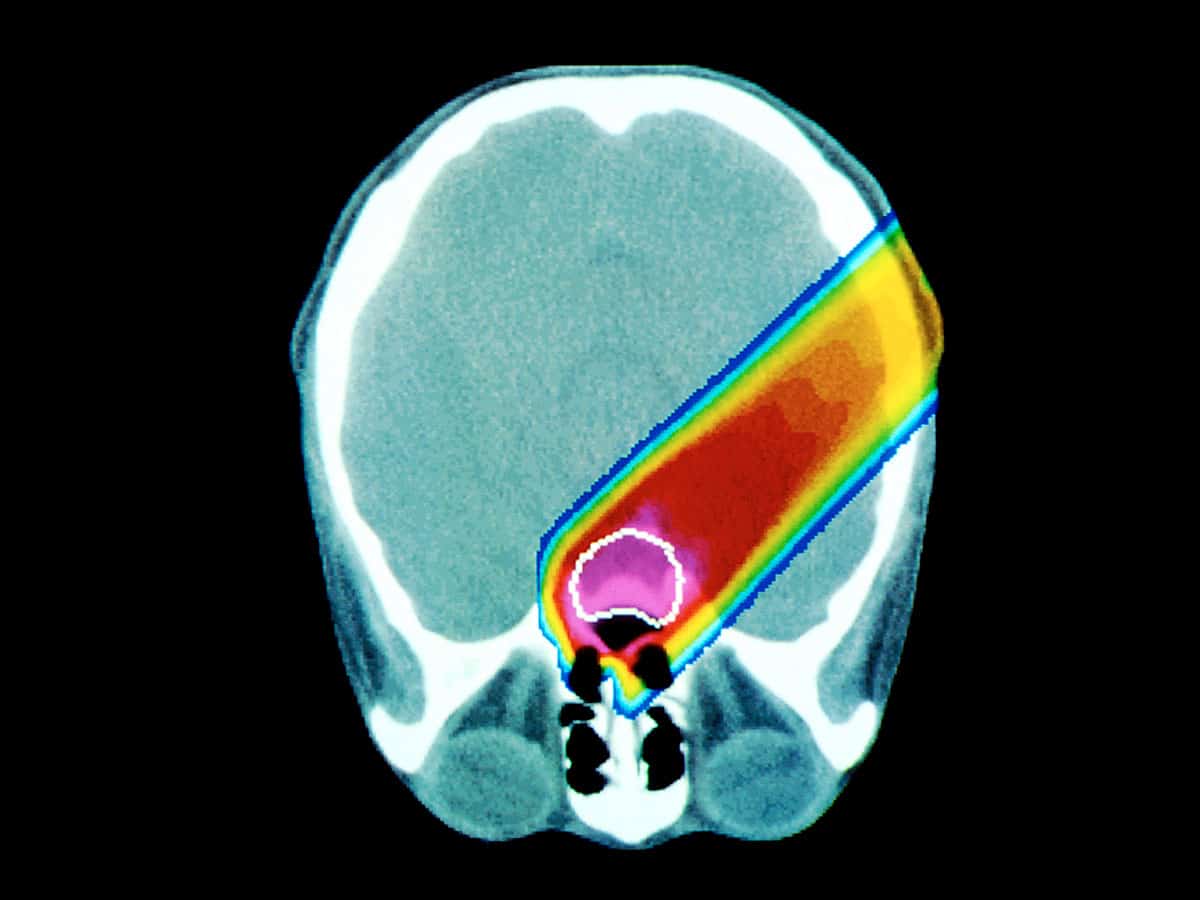

That treatment is hadron therapy, which exploits the fact that beams of protons and other hadrons can almost magically penetrate human tissue before releasing their energy at a well-defined depth. Hadron beams can therefore kill tumour cells while sparing healthy tissue, making them ideal for treating certain cancers – notably the potentially lethal eye cancer ocular melanoma – because the patient suffers less and the success rate is higher. Gamma rays, X-rays or electrons, in contrast, tend to dump their energy over a much greater volume.

Particle therapy has emerged as a by-product of high-energy physics – in fact, the first treatment took place at the Lawrence Berkeley National Laboratory in 1954 – but making it more widely available is a challenge. The snag is that the accelerators currently used to create beams of protons and other heavy ions are large and expensive, and the gantries that steer the beam across a tumour are the size of a small house. But one solution that could put particle therapy within the reach of most hospitals is laser-driven acceleration, which involves firing a very short yet intense laser pulse into a jet of gas, thin foil or thicker target.

As the intense pulse travels through the target, it rips nearby electrons away from the positive nuclei, thus creating a huge electric field gradient in its wake. This field has a large accelerating potential that can be thousands of times that of a conventional accelerator. A laser-driven hadron accelerator can therefore, in principle, be relatively compact. Table-top lasers have already been used to accelerate protons to tens of mega-electron-volts, approaching the 70 MeV needed to treat ocular cancer. However, we need to find ways of boosting their energy to 200–300 MeV to kill tumours lying deeper within the body.

Commercially available laser systems that can deliver such energies should be available in about 10 years, although it will probably take a further decade or so before they become routinely used to treat patients in hospitals. One problem with laser acceleration is that it delivers particles in pulses, rather than as a continuous beam. Techniques will therefore have to be devised to ensure the pulses are intense and numerous enough that patients get enough of a dose without having to lie perfectly still for long periods. In fact, the pulses could be a virtue as the magnets needed to scan the proton beam across a treatment area would then not have to be as big.